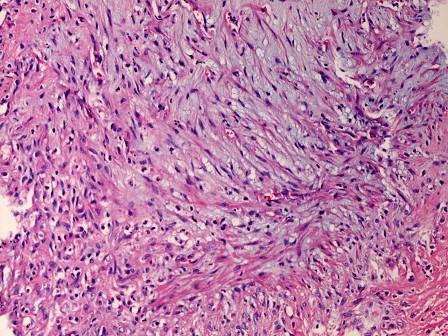

问题 某患者行二尖瓣置换术,二尖瓣的镜下改变如图所示,可见灰蓝色黏液样基质,发生了何种变性 ( )

选项 A.玻璃样变 B.淀粉样变 C.色素沉着 D.黏液样变性 E.水变性

答案 D